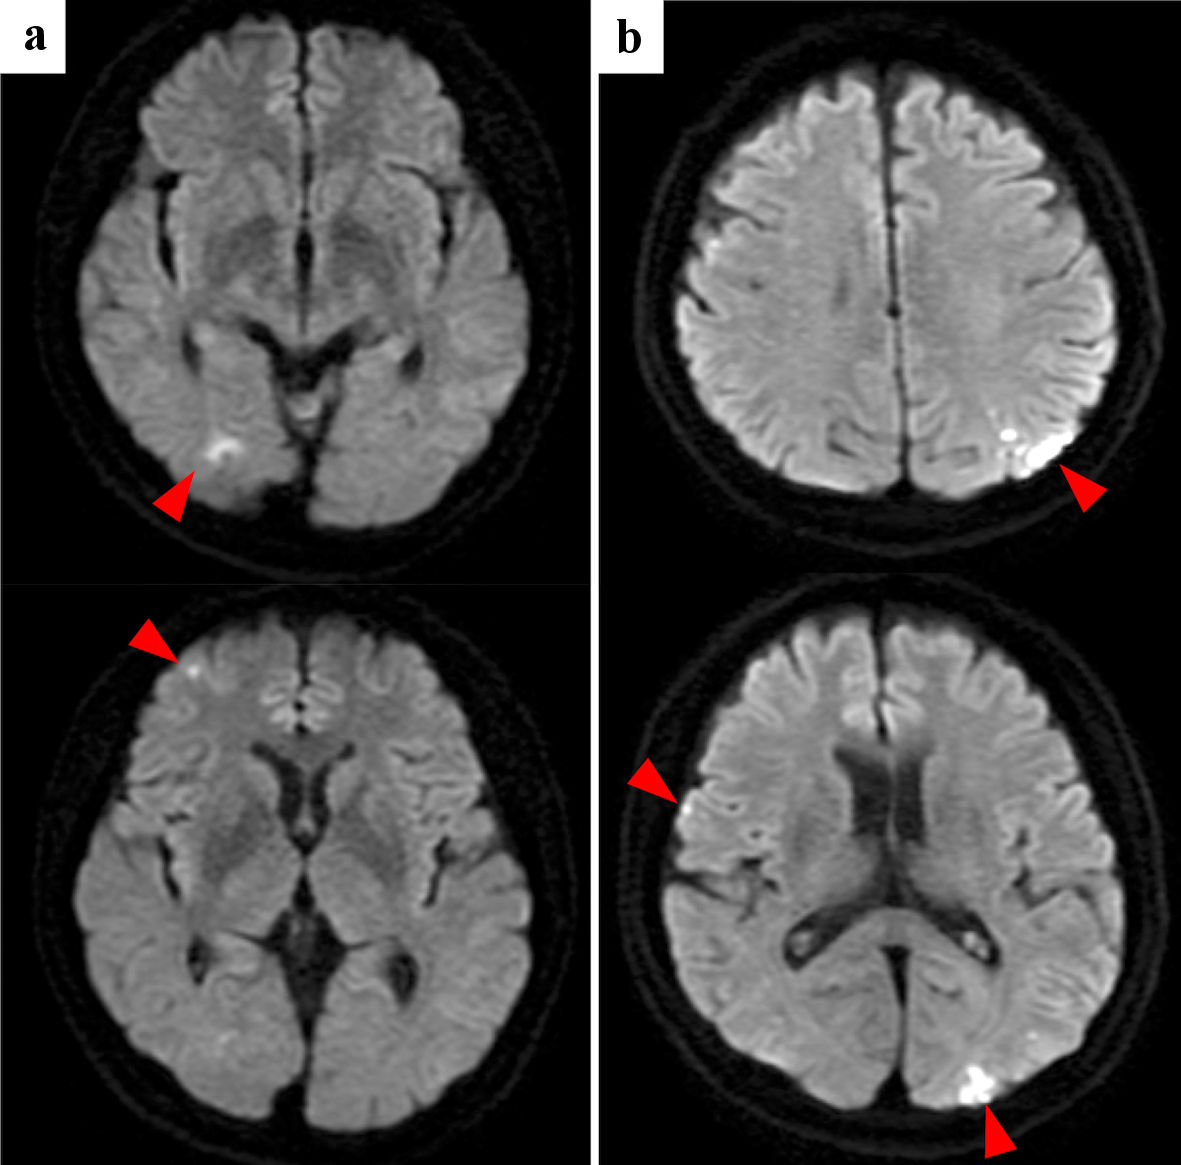

Multiple and coincidental cerebral infarctions in bilateral multiple vascular territories were the most frequent radiological features shown by brain MRI (n = 9). As representative cases, the images of cases 1and 2 are shown in Figures 1 and 2, respectively. Nine had neurological symptoms at the time of the initial cerebral infarction, while one was asymptomatic.

![]() Click for large image | Figure 1. Case 1: brain diffusion-weighted MRI of initial cerebral infarctions (a) and recurrent cerebral infarctions (b). Red arrowheads point cerebral infarctions. MRI: magnetic resonance imaging. |

Recurrent cerebral infarctions were observed in six patients, all within 50 days. Five had recurrence despite anticoagulation therapy. Among the four patients who started and continued heparin at the initial onset, one had a recurrence. On the other hand, among the other four patients whose initial treatment was anticoagulants other than heparin or who did not continue heparin, all four had recurrences. Two patients did not receive anticoagulants at the initial onset because of their poor general condition. While heparin was used for initial treatment in four patients, it was used in seven patients during the course of treatment. Moreover, three patients were discharged using self-injection of subcutaneous heparin calcium at home. Since low-molecular-weight heparin has not been approved by Japanese medical insurance for the treatment of cerebral infarction, we used intravenous unfractionated heparin or subcutaneous heparin calcium.